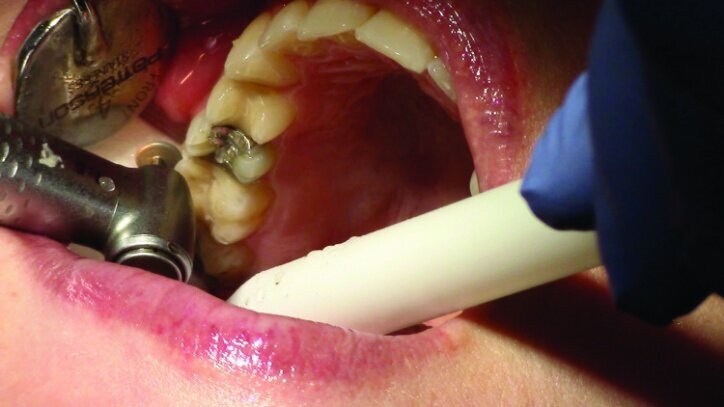

This patient presented for restorations of teeth #3 and #4 (Fig. 1a). Because of the size of the existing restorations, these teeth were diagnosed as structurally compromised (Figs. 1b, c). The prognosis without treatment was fair.

The restorations were to be completed with PlanScan chairside CAD/CAM technology in the same visit.

Depth guide cuts were made using a 330 bur, which has a 2 mm cutting surface (Figs. 2a–3b). This ensures 2 mm of occlusal reduction to accommodate 2 mm of material thickness on the occlusal surface of the restoration.

Gross occlusal reduction was completed using a KS7 bur to the depth cuts (Figs. 4–8b, 9c). Adequate clearance was verified with a 2 mm prep check from Common Sense Dental Products.

After gross occlusal reduction was completed, the remaining enamel ring was measured (Figs. 9a, b). The enamel rings were noted to be 1.5 mm, and the teeth were prepared for adhesively retained restorations. If the enamel rings were less than 1 mm, the teeth would have been prepared on the axial walls to create retention for cohesively retained crowns.

The remainder of the existing composite resin in #3 and the amalgam in #4 were removed. The occlusal surfaces of the preparations were blended into the interproximal areas using a KS2 bur to create smooth preparations (Figs. 10–15c). There was no retention or resistance form prepared to retain the restorations.